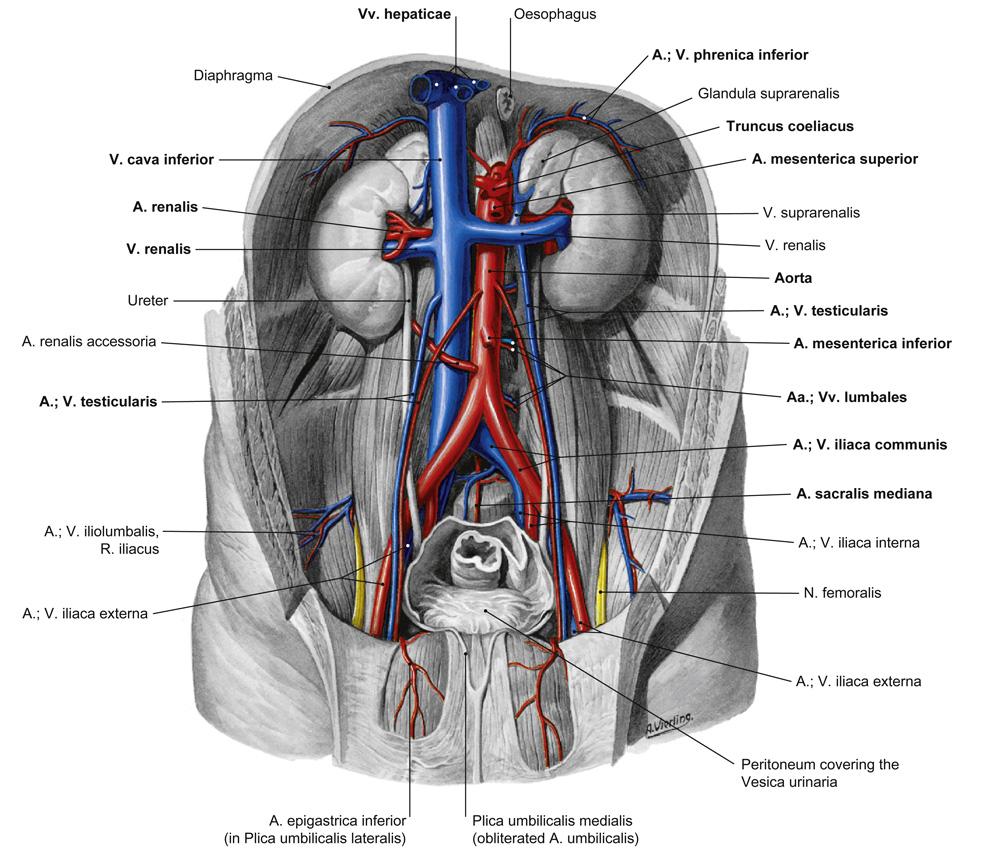

Fig 3.21: Aorta abdominalis

|

|

Fig 3.25: Aorta abdominalis - pare viscerale takken

|

|